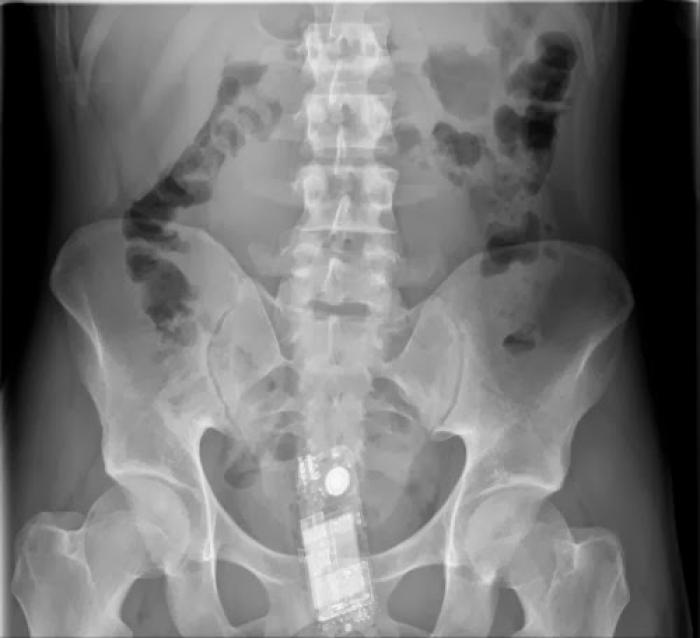

Razele X ne dovedesc că oamenii "pierd" adesea o mulțime de lucruri în propriul corp.